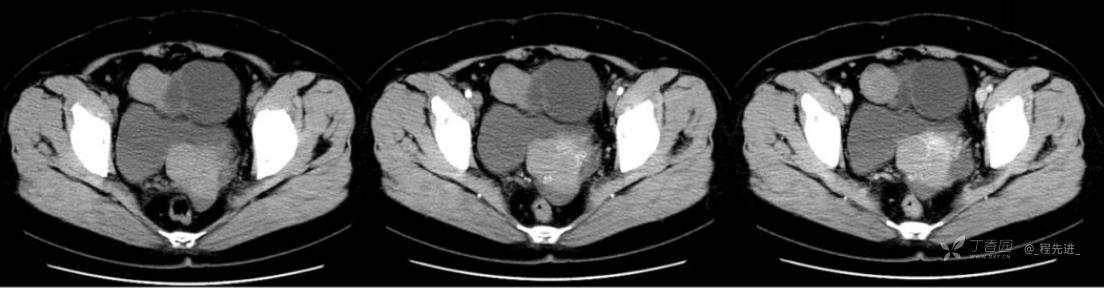

1月特别精彩病例|中老年女性,盆腔包块近半年持续增大【病理已公布】

患者年龄:53岁

简要病史:4年前体检时发现盆腔包块及子宫肌瘤,近半年复查盆腔彩超发现包块持续增大,近1年月经欠规律,伴腰、腹胀。

体格检查:宫颈举痛(+),子宫增大,质地中等,活动可,无压痛;右下腹轻压痛,无反跳痛,左侧附件区未扪及明显包块,无压痛。

阴式彩超:子宫约65*58*44mm大小,子宫肌层可见多个低回声块影,较大的为35*27mm(位于子宫前壁下段偏右侧壁),边界清,内回声欠均匀,后方回声衰减。考虑子宫多发肌瘤。子宫后壁可见一混合回声包块,大小约31*20mm,边界不清,内呈强弱回声,分布不均,考虑子宫腺肌瘤,其他疾患待删。子宫内膜厚6mm,宫颈可见多个囊性暗区,边界清,内透声好,后壁效应增强,较大的为15*11mm。子宫前方偏左侧可探及一大小89*75mm囊性肿块,边界清,壁薄光滑,内透声好,可见分隔光带